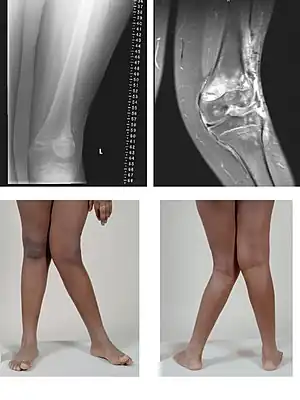

| Valgus Deformity MRI and photograph | |

A valgus deformity is a condition in which the bone segment distal to a joint is angled outward, that is, angled laterally, away from the body's midline.[1] The opposite deformation, where the twist or angulation is directed medially, toward the center of the body, is called varus. Common causes of valgus knee (genu valgum or "knock-knee") in adults include arthritis of the knee and traumatic injuries.

Knee arthritis with valgus knee

Rheumatoid knee commonly presents as valgus knee. Osteoarthritis knee may also sometimes present with valgus deformity though varus deformity is common. Total knee arthroplasty (TKA) to correct valgus deformity is surgically difficult and requires specialized implants called constrained condylar knees.